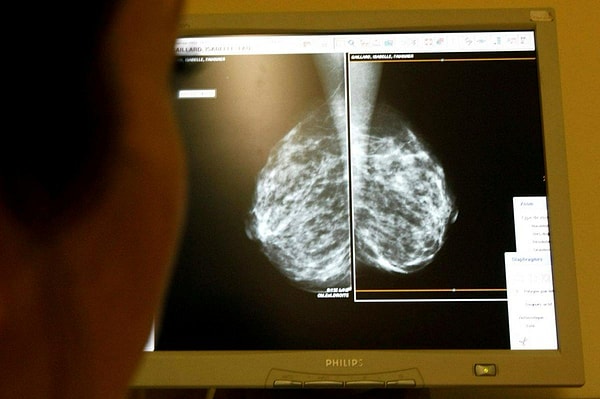

Искусственный интеллект, разработанный исследовательским отделом Google в сфере здоровья и медицины Google Health и британским Имперским колледжем, диагностировал рак молочной железы лучше, чем врачи.

Программа была подготовлена шестью врачами на основе маммографических снимков 29 000 женщин.

Согласно исследованию, опубликованному в научном журнале Nature, разработанный алгоритм был так же хорош, как два доктора, которые исследовали рентгеновские снимки.

Согласно данным, искусственный интеллект обнаружил раковую опухоль в 2,7 процентах маммографических снимков, в которых рентгенолог не увидел опасности.

Программа, которая может оценивать маммографические снимки за несколько секунд, может повысить точность диагностики рака молочной железы и облегчить бремя радиологов, которые примут окончательное решение.